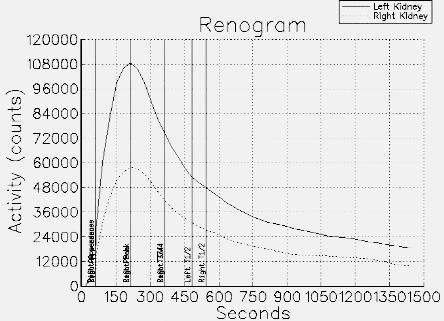

CaseTN04

- Age/Sex: 56M

- Chief Complaint: 腎移植のドナー

- Clinical Course:

- Lab. Data:

- Images:

- Tc-99m MAG3,坐位

- Blood flow

phase

- Cortical-Excretory

phase

- renogram

- DIP 10 min (左)20min

(右)立位

- X-CT:

左右の容積計測値 R/L比=0.8